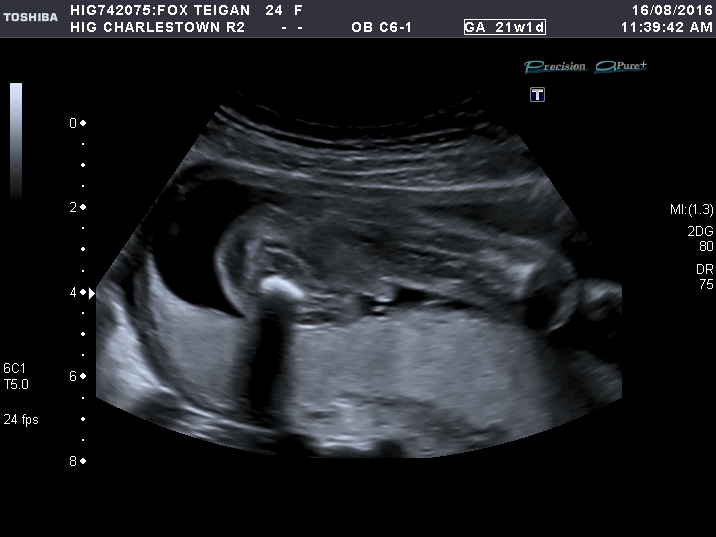

21 week scan :)

Sorry forgot to mention the more I look at the 21 weeks I think maybe its the cord? they had there legs shut for most of the scan to the very last try at a peak what's inbetween.

That's definitely a boy!! Huge congrats [emoji170]!!

That's a boy alright ;)

Boy!!

Blimey that's one heck of a boy! Congrats!!